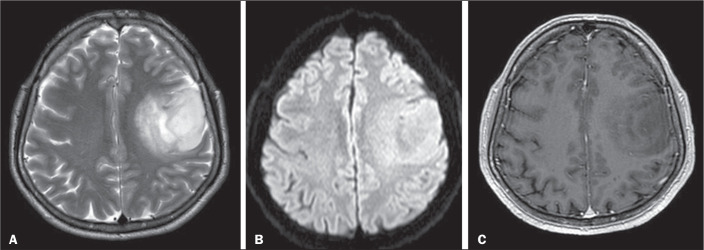

Objective: To determine the correlation of conventional and diffusion-weighted imaging findings on magnetic resonance imaging (MRI) of the brain, based on Visually AcceSAble Rembrandt Images (VASARI) criteria, with the histopathological grading of gliomas: low-grade or high-grade.

Materials and methods: Preoperative MRI scans of 178 patients with brain gliomas and pathological confirmation were rated by two neuroradiologists for tumor size, location, and tumor morphology, using a standardized imaging feature set based on the VASARI criteria.

Results: In the univariate analysis, more than half of the MRI characteristics evaluated showed a significant association with the tumor grade. The characteristics most significantly associated with the tumor grade were hemorrhage; restricted diffusion; pial invasion; enhancement; and a non-contrast-enhancing tumor crossing the midline. In a multivariable regression model, the presence of enhancement and hemorrhage maintained a significant association with high tumor grade. The absence of contrast enhancement and restricted diffusion were associated with the presence of an isocitrate dehydrogenase gene mutation.

Conclusion: Our data illustrate that VASARI MRI features, especially intratumoral hemorrhage, contrast enhancement, and multicentricity, correlate strongly with glial tumor grade.